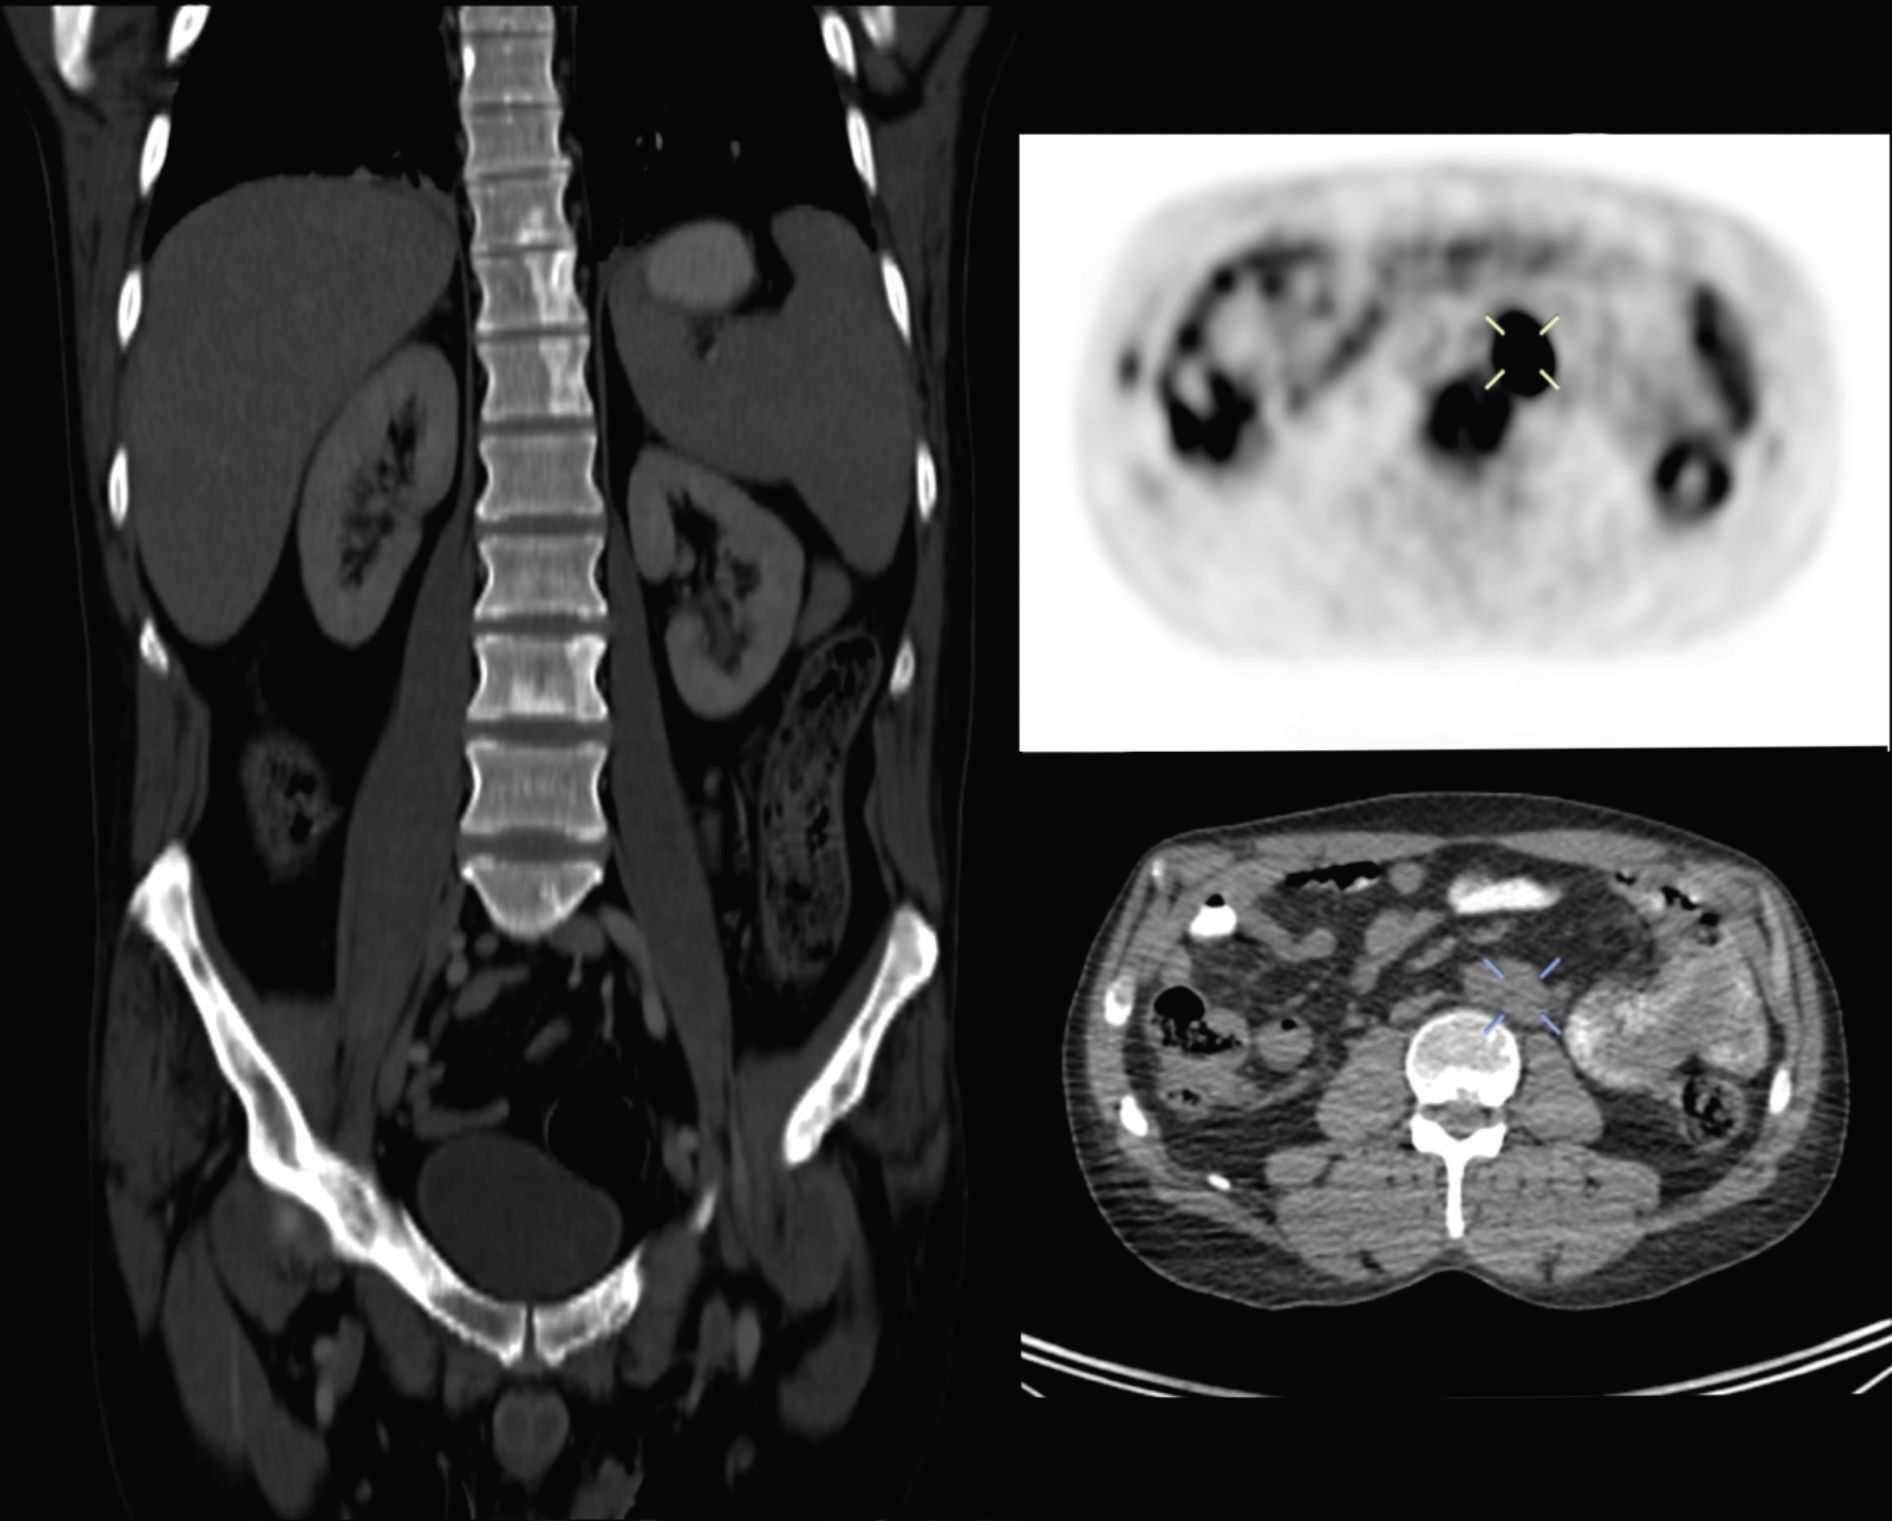

Figure 4 PET-CT imaging one-year post-relapse evidencing osseous lesions and lymphadenopathy.

One year after initial CNS iEMR, the patient developed overt bone marrow relapse (BMR), as evidenced by development of bone pain throughout the lumbosacral region, and the appearance of multiple blastic and lytic lesions throughout the appendicular and axial skeleton. A positron emission tomography-CT scan documented abdominal lymphadenopathy (Figure 4). With this rapidly progressive picture, the patient was transitioned to supportive care and died 2 months later.